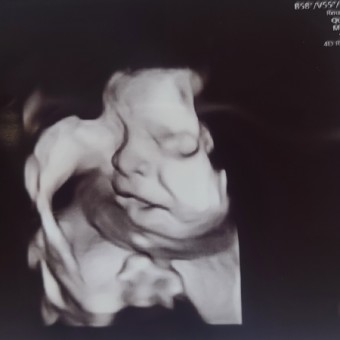

Karen Joyce's Baby Registry

Karen Joyce Apalla-Goldstein & Max Goldstein

March 9, 2026